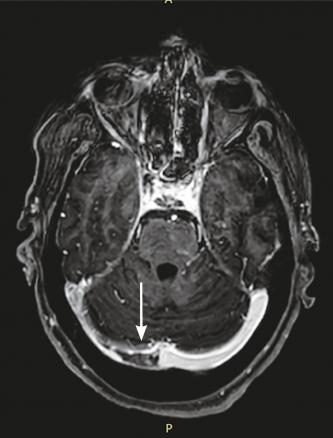

Cette femme de 45 ans était admise aux urgences à la suite d’une hémiplégie gauche. Une imagerie par résonance magnétique (IRM) cérébrale montrait un accident vasculaire cérébral ischémique aigu du territoire de l’artère cérébrale moyenne droite (fig. 1 ) avec occlusion de l’artère carotide droite. Par ailleurs, il y avait un comblant otomastoïdien droit (fig. 2 ) avec collection abcédée parapharyngée homolatérale (fig. 2 ) et thrombose de la veine jugulaire interne droite étendue au sinus sigmoïdien et latéral (fig. 3 ). Après 21 jours d’antibiothérapie intraveineuse combinée à l’anticoagulation, l’IRM de contrôle montrait une recanalisation de la carotide interne et de la veine jugulaire interne.